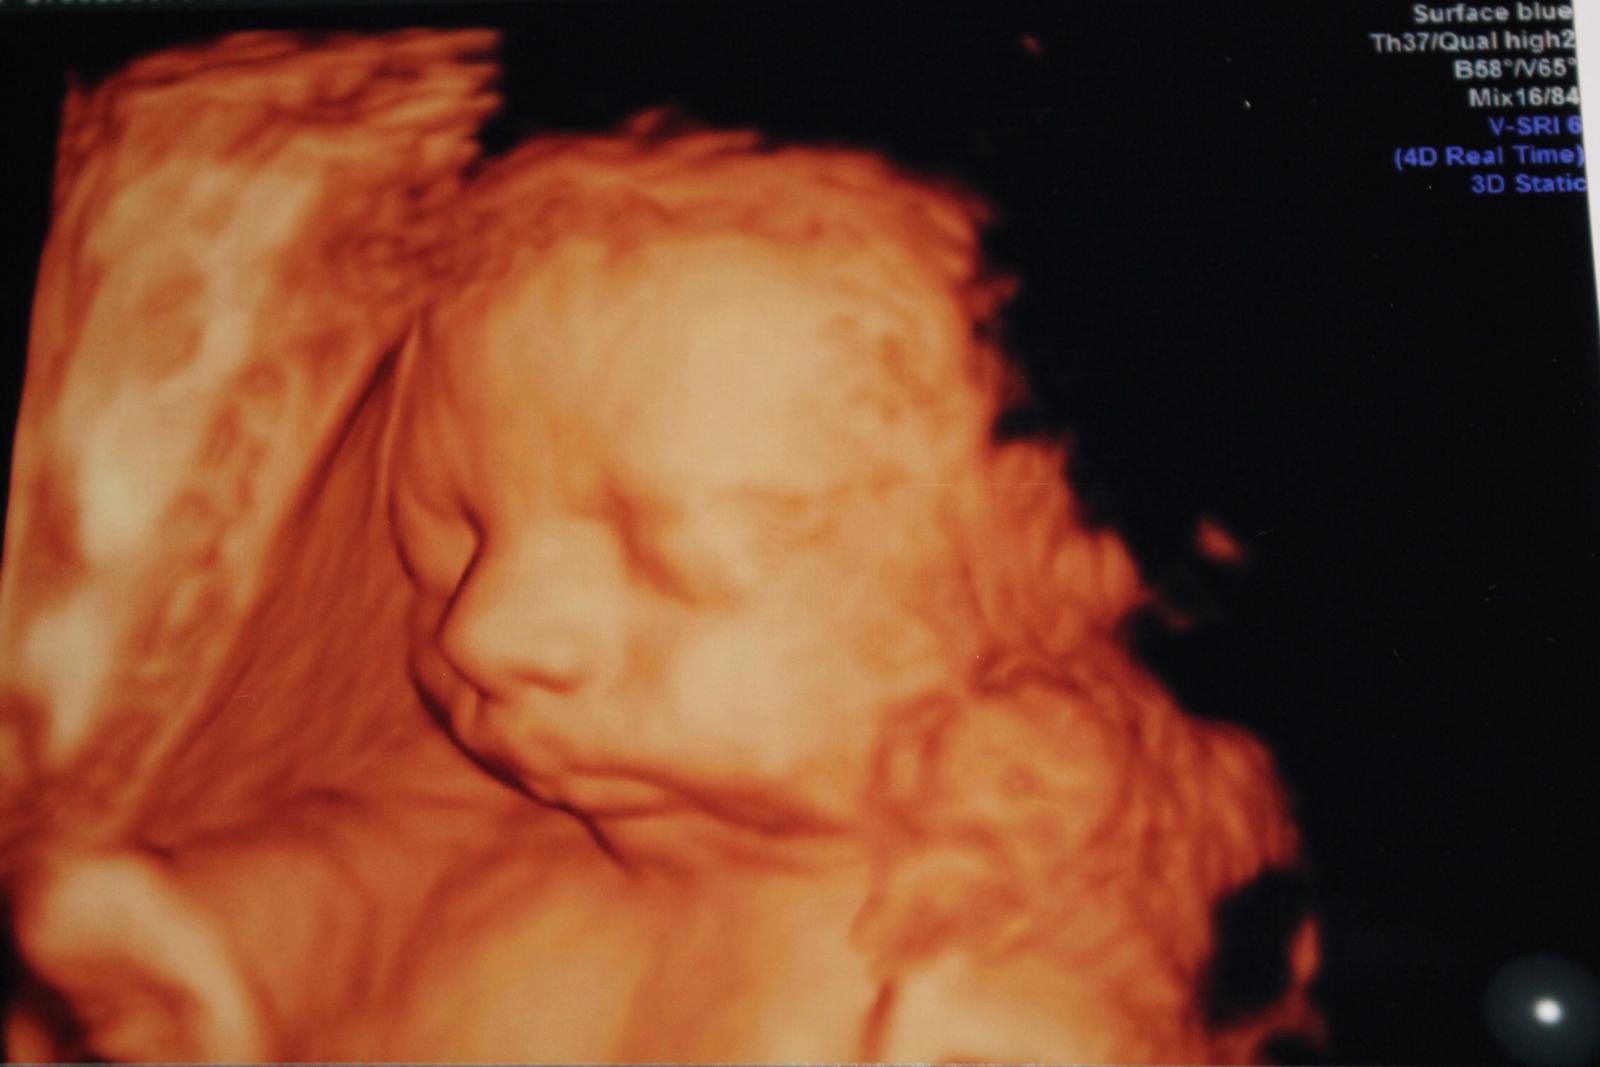

My sme dnes boli v MT u Dr. Grochála na tom vyšetrení srdiečka....strašne milý človek, ktorý nám všetko povysvetľoval....pozrel všetky orgány a všetko je v poriadku....tak som šťastná ako blcha...a potvrdil nám, že sme 31+4 a počula som, že vačšinou trafil termín porodu presne, takže nás presunul na 28.10...a najviac ma prekvapilo jeho priberanie: v utorok 1710 g a dnes 1855 g...no asi si bere všetky živiny, lebo ja nepriberám....naposledy za 3 týždne 0,5 kg...a predtým som bežne aj 2-3 kg za taký istý čas...a konečne sa podarilo urobiť fotku tváričky, síce stála 8 eur, ale čert ho ber...peniaze boli a budú....tak už vieme ako bude asi vyzerať...fotku pridám neskor, lebo teraz ešte periem vecičky...